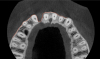

Fig 3. Tomographic images revealed a tridimensional defect extending to the apical third of teeth Nos. 6 and 8, a buccal bone dehiscence on tooth No. 5, and associated thin labial plates.

Figure 3

Fig 4. Tomographic images revealed a tridimensional defect extending to the apical third of teeth Nos. 6 and 8, a buccal bone dehiscence on tooth No. 5, and associated thin labial plates.

Figure 4

Tomographic images revealed a large tridimensional defect, with vertical and horizontal loss of bone extending to the apical third of teeth Nos. 6 and 8. Additionally, a buccal bone dehiscence was evident on tooth No. 5, and thin labial plates secondary to the orthodontic movement were present in several areas (Figure 3 and Figure 4).